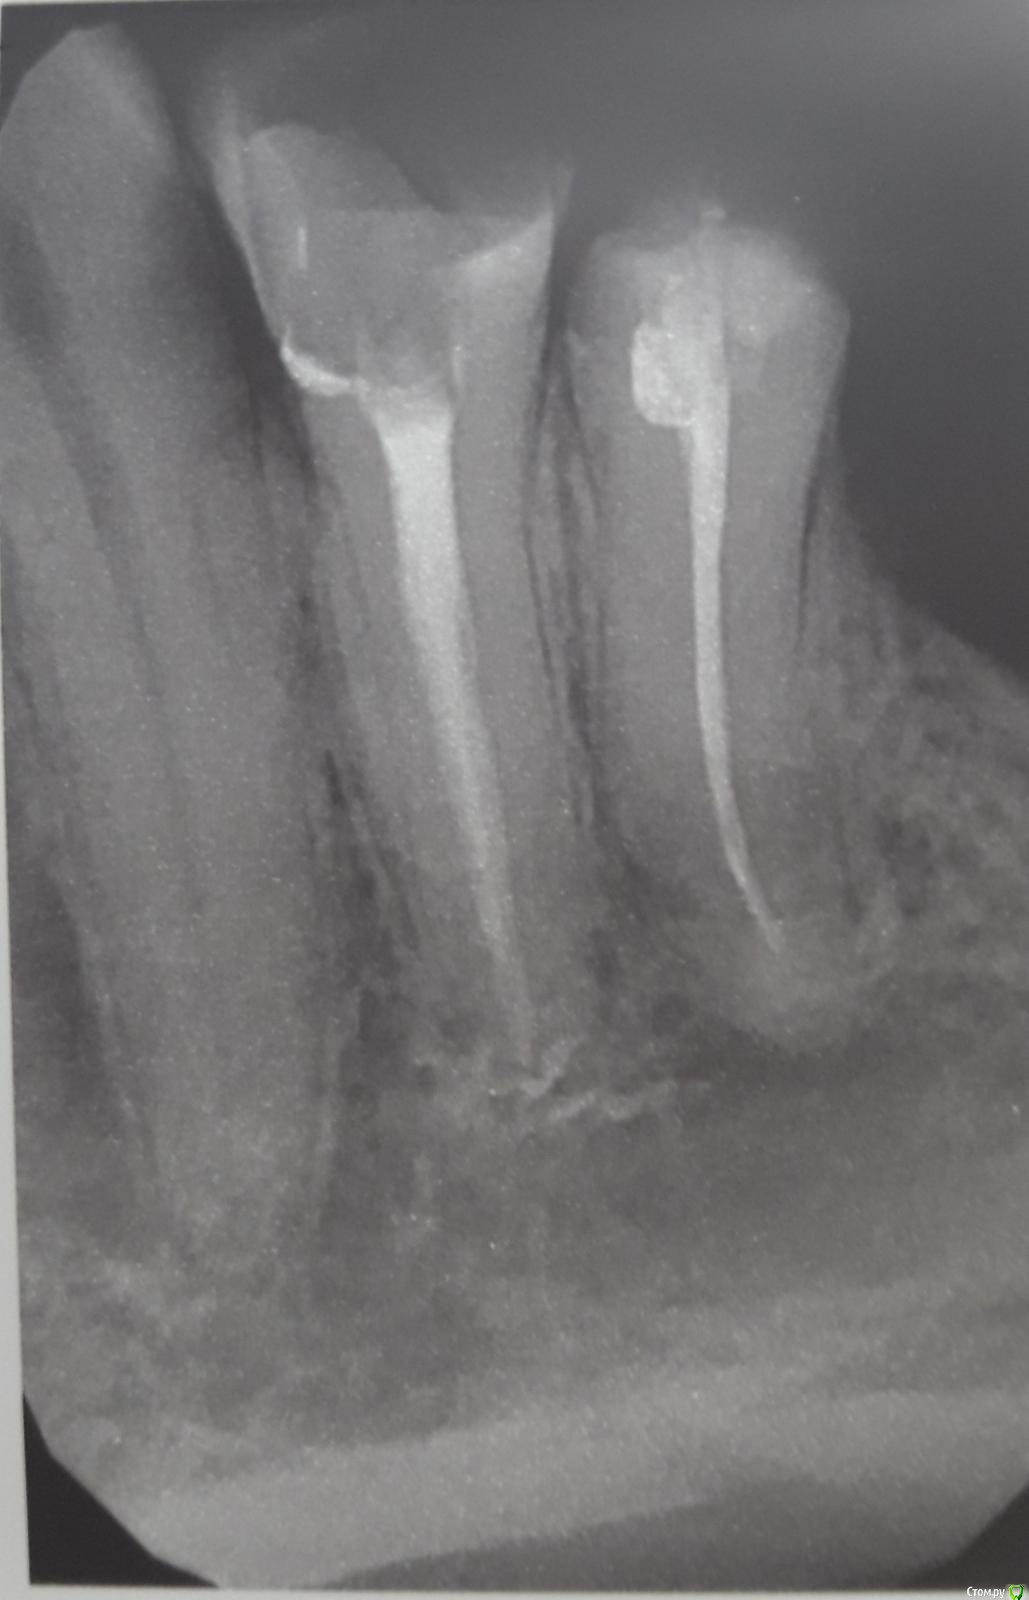

Всем доброго дня. Спасибо за внимание. 5й зуб, депульпирован больше 10 лет, был под группой коронок, коронки сняты 4 года назад из-за удаления 6го зуба. Когда меняли пломбу, врач обратил, что от зуба идет плохой запах, пыталась переделать канал, но не смогла его распечатать, в итоге поставили пломбу и забыли. Порядка года назад начали появляться боли по ночам в районе этого зуба, при нажимании пальцем на щеку на нижней челюсти в районе зуба возникают несильные неприятные ощущения, но после приема найза пропадают и через некоторое время всё повторяется. Таким образом, насколько я понимаю, пролечить канал зуба нельзя, а особых проблем на снимке не видно, в тоже время проблемы с периодическими болевыми ощущениями не уходят, а повторяются (болит - найз - передышка - болит - найз). Готов расстаться с зубом, но прислушаюсь к рекомендациям. Еще раз спасибо!

Таким образом, насколько я понимаю, пролечить канал зуба нельзя, а особых проблем на снимке не видно

Воспаление есть на снимке. Но снимок сам по себе не очень четкий.

Если раньше не удалось полностью обработать канал, то это ничего не значит.

Сделайте КТ